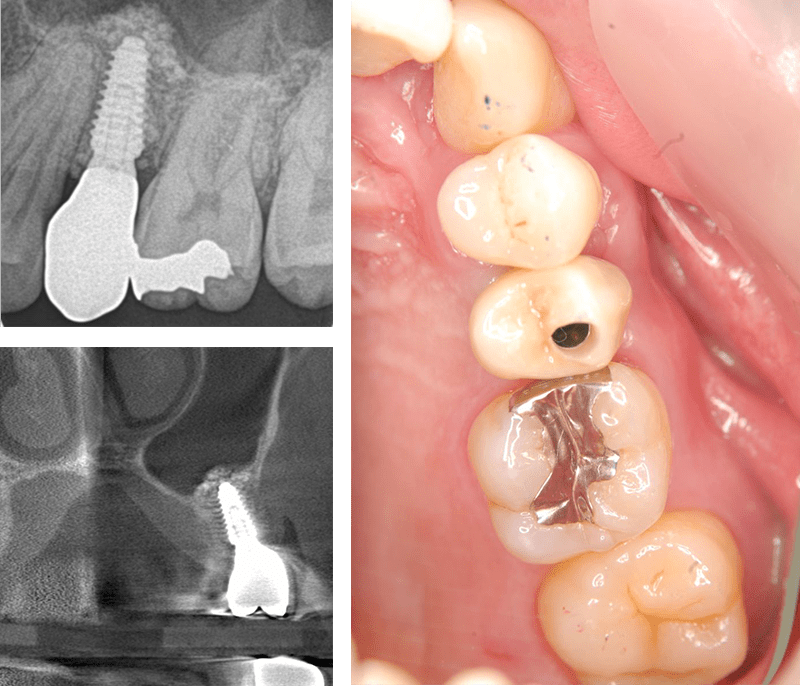

症例4【50代女性】左上6 副鼻腔膜を挙上しインプラント埋入 左上5 歯根破折の為インプラント埋入

治療前

左上5の歯根破折

治療後(10年経過)

主訴 左上奥歯で物が噛めない。入れ歯は煩わしいので、インプラントを希望。

左上第一大臼歯欠損部位は、骨の高さが3~4㎜しかなく、造骨の為にソケットリフト(骨造成)を行い、骨の高さを確保しインプラントを埋入。

約半年の免荷期間を経て、仮歯を装着、リハビリをし、約7ヶ月後にメタルボンド(金属焼付ポーセレン)を装着。

その後、左上第二小臼歯の歯根破折の為に、2本目のインプラントを埋入。(抜歯即時埋入)

リスクとしては、ソケットリフト(骨造成)による一過性の副鼻腔炎が起きる可能性がある。まれに洞底膜が破れる可能性がある。ただし、膜は約3週で再生するので、膜の回復を待ち、再オペを行う。

費用 111万(オペ。ソケットリフト・人工骨・採血による濃縮血小板生成・仮歯・最終補綴物まで含む)